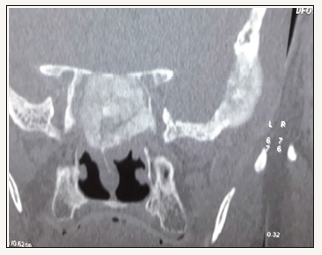

Figure 1:

A 79-year-old male patient presented with history of recurrent bleeding from nose and naso pharynx. Diagnostic nasal endoscopy did not reveal any obvious lesions. There was no generalized bleeding tendency. Coagulation profile was normal. There was no hypertension. Renal and hepatic functions were normal. Treatment history for carcinoma prostate 10 years back from a premier medical college of South India was available. When he came to us serum PSA was 100mg/ml and acid phosphate was 63 units CT scan of the PNS showed an osteo blastic expansile lesion of the Sphenoid (Figure 1). A biopsy was not taken as it was very clear that he had secondaries in the Sphenoid from his prostate carcinoma he had, because of the following 3 reasons (Figure 2).